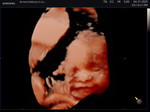

Hello mommies im currently close with my 19th week of twin pregnancy, is it normal if may nipple discharge, pansin ko sa left side lng ng boobie and it happens while im asleep nagigising nalang ako basa damit ko ?